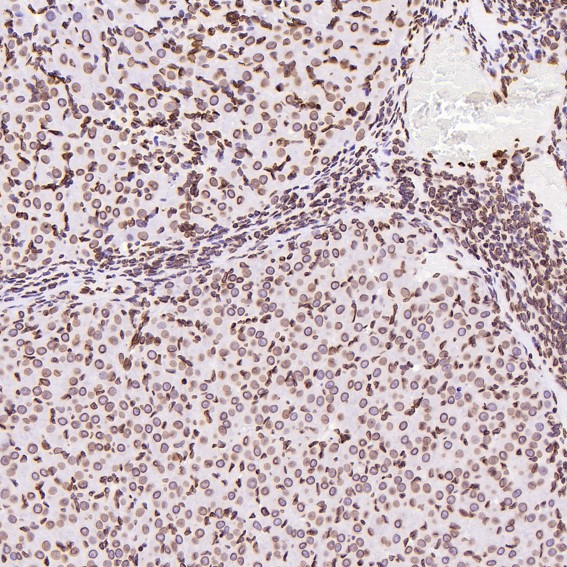

Immunohistochemical analysis of paraffin-embedded Rat ovary, using the Antibody at 1:200 dilution.

Immunohistochemical analysis of paraffin-embedded Human non-Hodgkin's lymphoma, using the Antibody at 1:100 dilution.